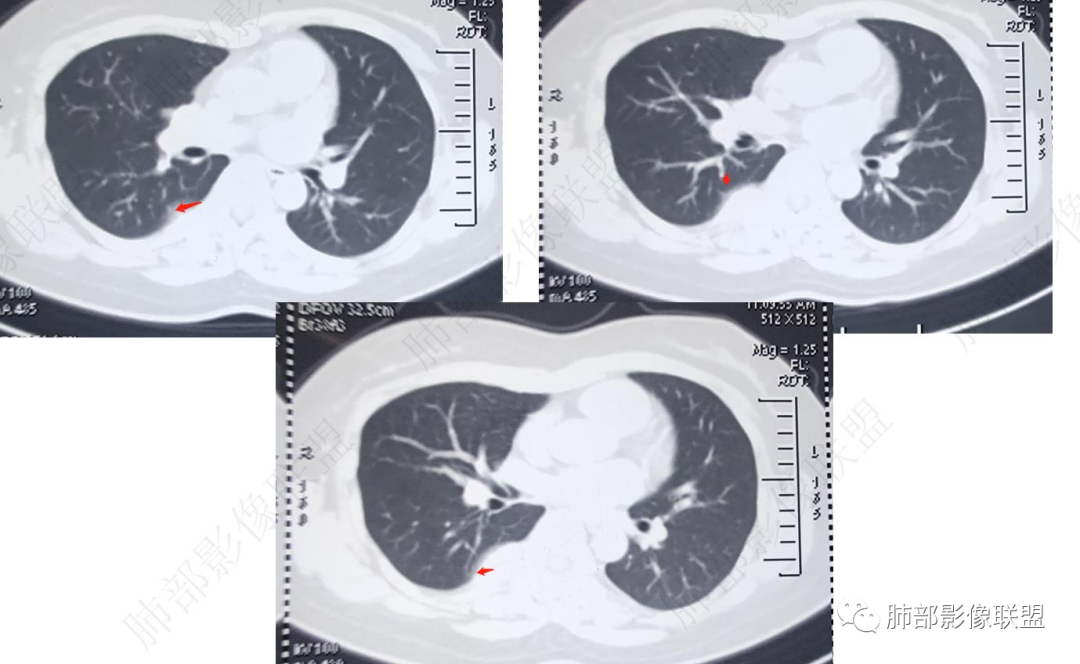

CT表现: 大多数病灶呈境界清楚的肿块影,呈蔓状生长,质地软,仅少部分与周围结构分界不清,平扫时肿块密度均匀或不均匀,肿块内可见小点状钙化、静脉石或血栓形成,偶尔可见脂肪密度影,增强后强化方式多样,呈典型的多灶性或弥漫性不均匀性强化,也可呈中心型或外周型强化,肿块内也可见强化的血管腔,在动脉期即能显示与纵隔大血管一样的强化。

中青年女性,胸痛就诊,CT检查发现右后纵隔占位,病灶位于后胸壁纵隔移行区,略呈卵圆形或梭形蔓延,质地软,等/稍长T1、显著长T2信号,T2W脂肪抑制序列“亮灯”样高信号,这种磁共振信号特征对血管瘤具有强烈提示意义!(实在是太亮了,严格意义上的肿瘤罕见)

病灶显著强化,强化与纵隔大血管相仿且同期,一般会提示是血管源性病变,如血管瘤,如果边缘结节样强化逐渐填充渐进,则提示可能为海绵状血管瘤。